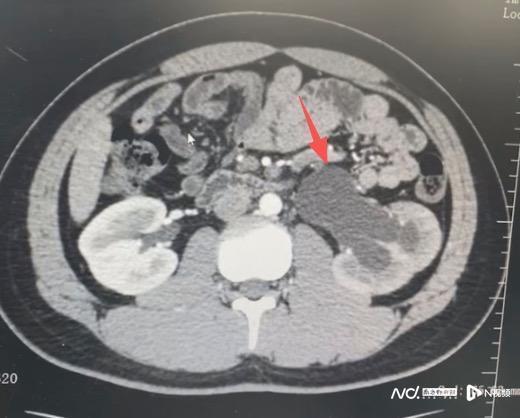

小宇本该在篮球场上挥洒汗水,却被突如其来的剧烈腰痛逼进了医院。在广州医科大学附属第五医院(简称“广医五院”)泌尿外科门诊,检查结果让家长后怕不已:导致小宇痛苦的并非简单的肌肉拉伤,而是一个从出生就潜伏至今的先天性输尿管狭窄,他的肾脏已因此出现中度积水。

据广医五院泌尿外科徐桂彬主任介绍,先天性输尿管狭窄是孩子出生时就存在的输尿管管道狭窄问题。输尿管作为肾脏向膀胱输送尿液的“水管”,一旦发生狭窄,尿液就会像堵塞的河道一样倒流回肾脏,导致肾积水。临床统计显示,这类疾病好发于男性患儿,且左侧更为多见。它最大的特点就是“早期无症状”,在轻度狭窄时,身体不会有任何不适。小宇的病情之所以潜伏了16年才被发现,正是因为平时缺乏针对性检查,直到肾脏被“撑”到极限,出现腰疼甚至可能摸到包块时才就医。